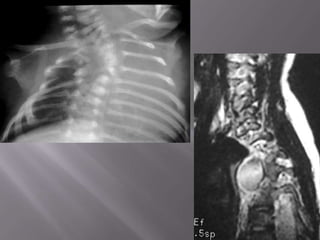

 This coronal T1-weighted, spin-echo image demonstrates the tumour well and shows

that it does not enter the spinal canal or encroach significantly on the adjacent foramina.

 IMAGING - The rib spaces and the intervertebral

foramina may be widened by the tumour.

 MRI - Variable T1-weighted signal intensity that

may be similar to spinal cord.

- high signal intensity peripherally and low

signal intensity centrally (target sign) on T2-W.

- 10% may extend appear as dumb-bell-shaped

masses with widening of the affected neural

foramen.